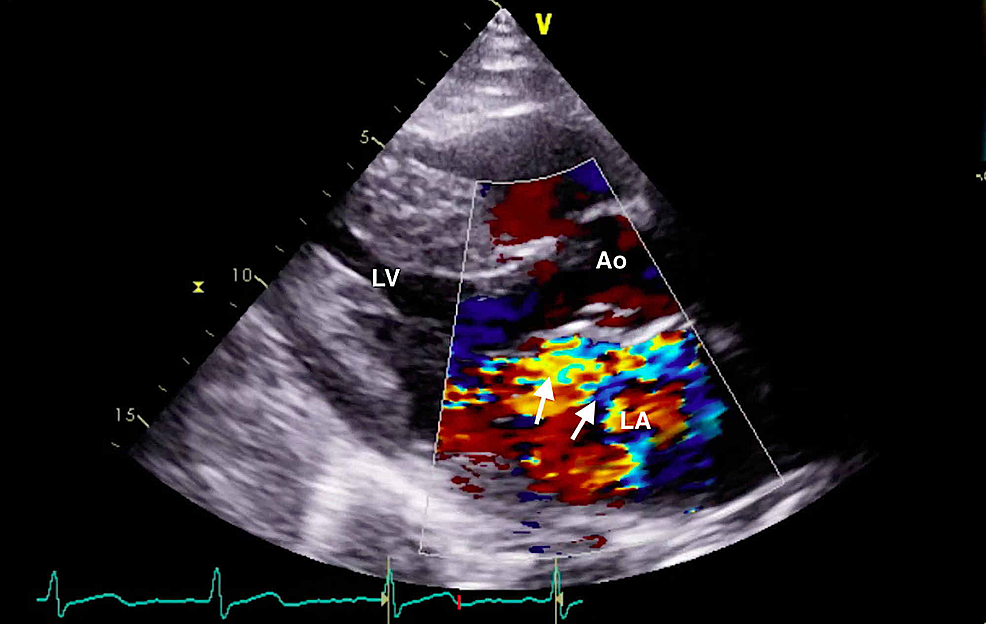

The clinical history was also concerning for an undiagnosed cardiomyopathy, particularly given the heart murmur appreciated on examination and his stated history of MVP for which the patient had never sought outpatient cardiology follow-up. Bedside LUS and FOCUS were then performed by emergency medicine resident physicians. LUS was notable for the presence of a diffuse B-line profile consistent with pulmonary edema (Figure 1). FOCUS was unremarkable for evidence of pericardial effusion, signs of right heart strain, or decreased LV contractility. However, FOCUS revealed a dilated left atrium (LA) and a suspected posterior FML, with the posterior MV leaflet seen protruding into the LA (Figures 2, 3; Videos 1, 2).

The constellation of FOCUS findings immediately prompted a formal comprehensive transthoracic echocardiogram (TTE) and emergent cardiology and cardiothoracic surgery consultations. TTE confirmed preserved LV systolic function, LA dilation, and flail motion of the posterior MV leaflet with severe eccentric MR (Figures 4, 5; Videos 3-5).

The major etiologies of acute MR include non-ischemic causes such as spontaneous ruptured chordae tendineae, infective endocarditis, and myxomatous leaflet degeneration and myocardial ischemia with associated papillary muscle rupture [12,13]. MVP is caused by myxomatous MV degeneration and has an estimated prevalence of 2%-3% [13,14]. MVP is the most common cause of severe non-ischemic MR in the United States, yet with only a small subset of patients developing major complications. There are two described forms of MVP, “classic” prolapse with myxomatous thickening of the mitral leaflets and “non-classic” prolapse with a more anatomically normal MV with lesser degrees of leaflet thickening; individuals with “non-classic” MVP have a better prognosis and less complications [13,15]. MVP may also be categorized by unileaflet and bileaflet subsets; interestingly, patients with unileaflet MVP have a higher incidence of flail leaflets than those with bileaflet MVP [16]. Our case patient likely had chronic “non-classic” unileaflet MVP which had degenerated to a posterior FML. It is notable that LA dilation was identified on bedside echocardiogram, suggesting that he had undiagnosed chronic MR. In contrast, patients with acute MR will have normal LA size. Consistent with our patient’s ultimate diagnosis, patients with FML will predominantly have severe MR with an eccentric mosaic regurgitant jet, usually with involvement of the P2 segment [17].